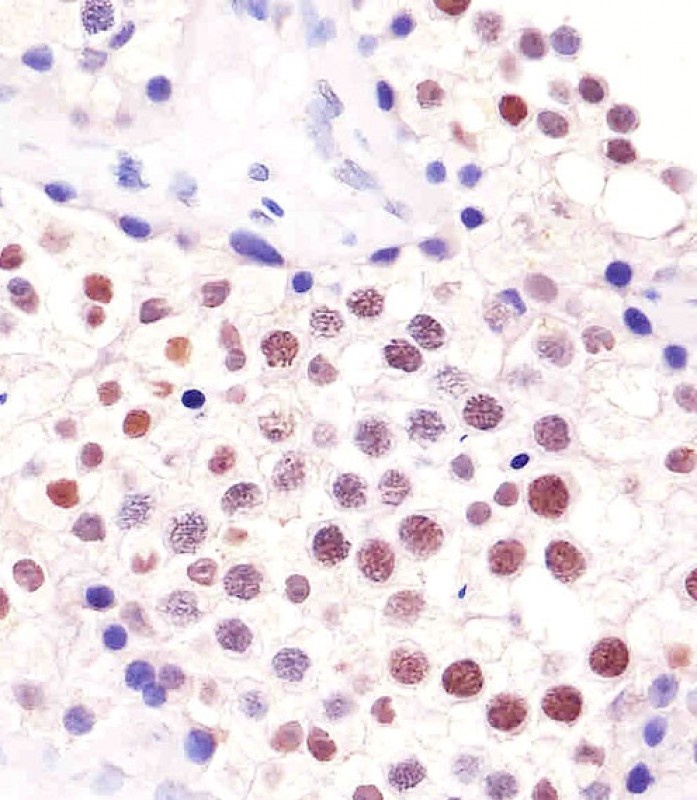

Immunohistochemistry of paraffin-embedded human ovary tumor slide using orb395161 (HuR Antibody) at dilution of 1:50.